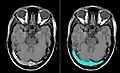

- Bildgebung bei zerebralen Thrombosen (zum Vergrößern Bilder anklicken)

-

-

Axiales SWI-Bild der scheitelnahen Duravenen. Die Thrombose ist im rechten Bild blau hervorgehoben.

Axiales SWI-Bild der scheitelnahen Duravenen. Die Thrombose ist im rechten Bild blau hervorgehoben. -